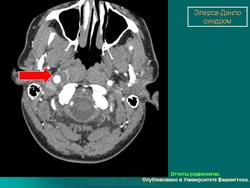

3. Васкулярный тип.

Наследуется по аутосомно-доминантному типу. Основные диагностические критерии: тонкая, прозрачная кожа, разрывы стенки артерий, кишечника и/или матки,обширные кровоизлияния, характерный фенотип. Дополнительные диагностические критерии: гипермобильность мелких суставов, разрыв сухожилий и мышц, косолапость, варикозное расширение вен с ранней манифестацией, артериовенозные каротидно-кавернозные фистулы, пневмоторакс/пневмогидроторакс, атрофия десневого края; положительный семейный анамнез, случаи внезапной смерти у близких родственников (многие пациенты не доживают до 50 лет из-за разрыва артерий или, что реже кишечника). Наличие двух и более главных критериев с большой вероятностью указывает на диагноз васкулярного типа СЭД и является показанием для лабораторной диагностики. Нередко отмечается характерный фенотип (узкий нос, тонкие губы, натянутая кожа, впавшие щеки и экзофтальм, обусловленный, в основном, снижением подкожно-жирового слоя). Надо отметить, что такой фенотип характерен для взрослых больных, а у детей он практически не выражен. Гипермобильность суставов обычно ограничена суставами пальцев. Максимальная частота спонтанных артериальных разрывов приходится на третью-четвертую декады жизни, но они могут возникать и раньше. Чаще всего вовлечены артерии среднего калибра. Беременность и роды могут осложняться разрывом матки и маточными кровотечениями, а также разрывом влагалища и промежности. Именно артериальные разрывы являются наиболее частой причиной внезапной смерти. Поэтому в качестве диагностических мероприятий рекомендуются, по возможности, неинвазивные процедуры. При этом типе СЭД сравнительно хорошо изучены изменения на молекулярно-белковом уровне. Этиологическим фактором являются мутации в гене коллагена IIIтипа.